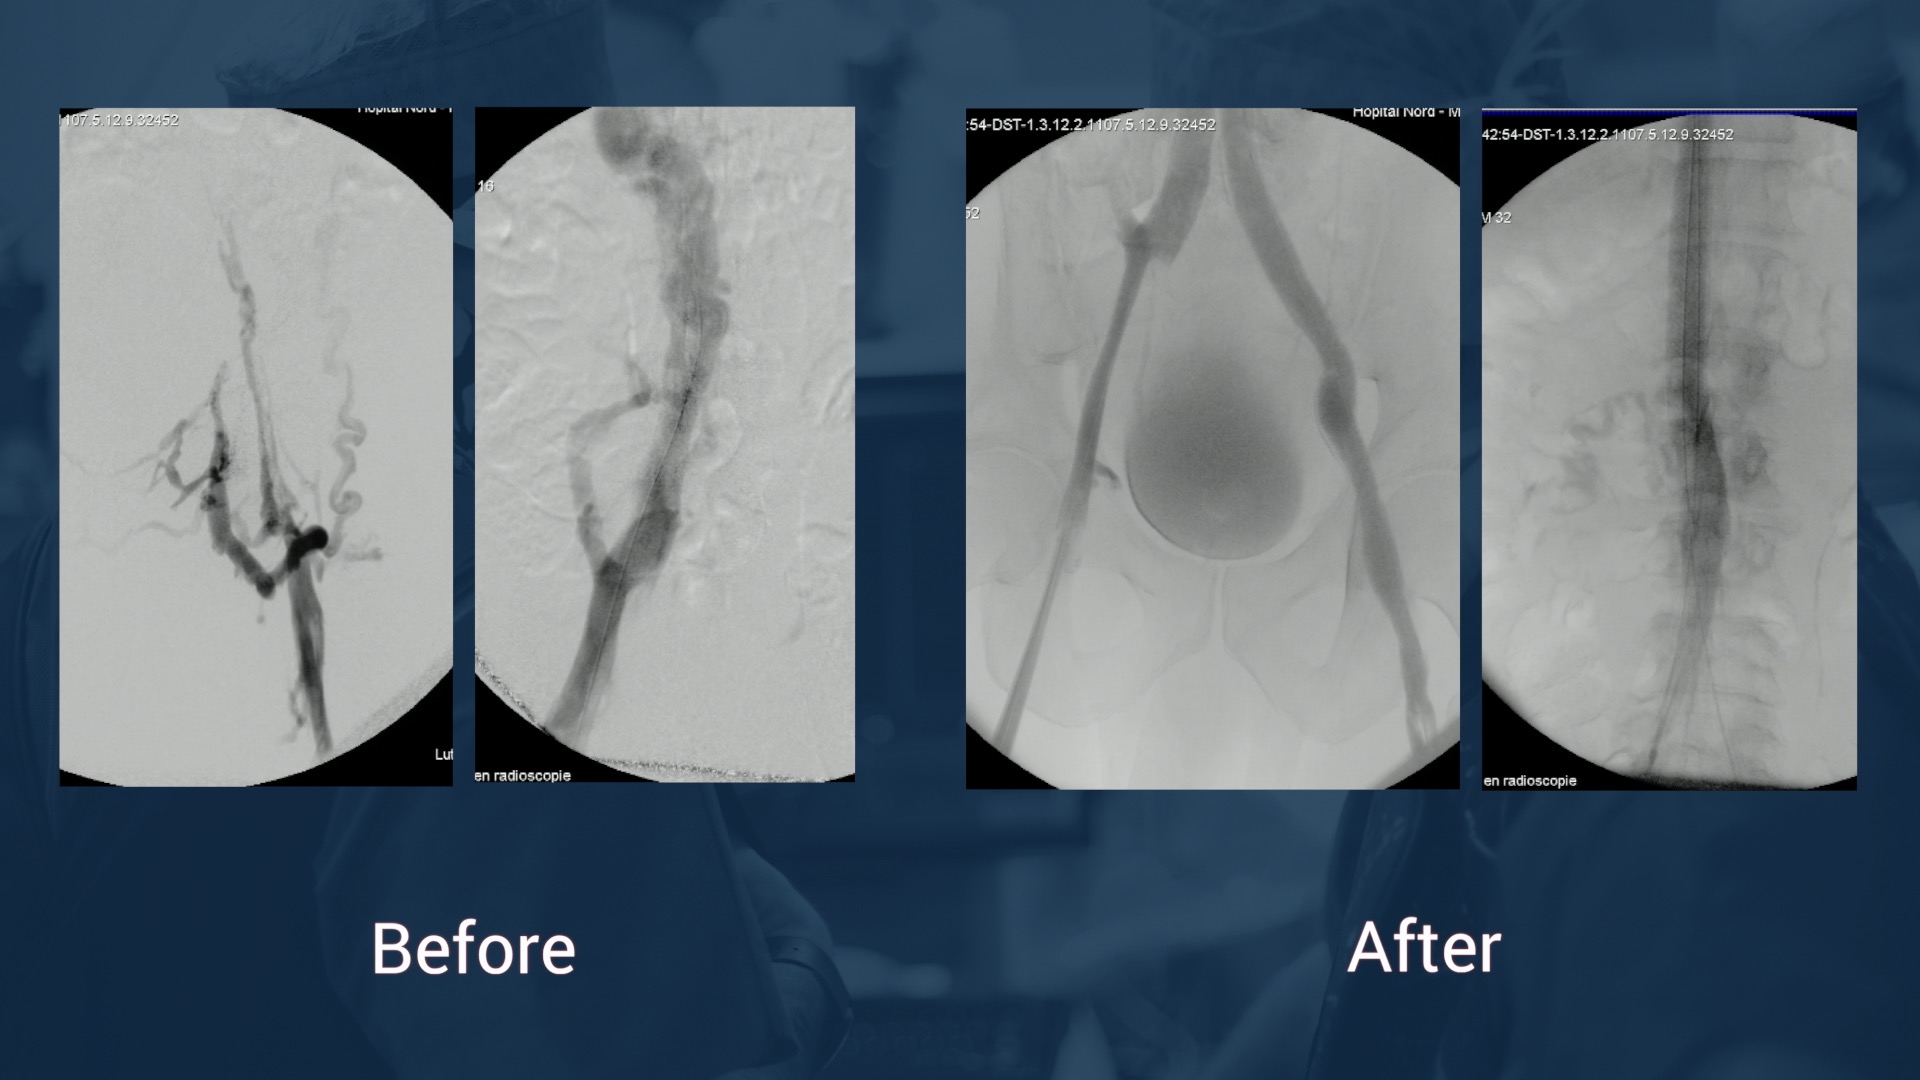

12.47 Case in box n°1: May-Thurner syndrome

12.57 Case in box n°2: May-Thurner syndrome

13.33 Case in box n°3: Left femoro iliac vein recanalization and stenting

13.41 Case in box n°4: Left femoro iliac vein recanalization and stenting